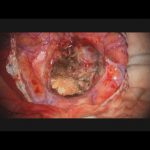

No.’23_132 手術前1

No.’23_132 手術前2

No.’23_132 摘出 前

No.’23_132  摘出 中

No.’23_132 摘出 後